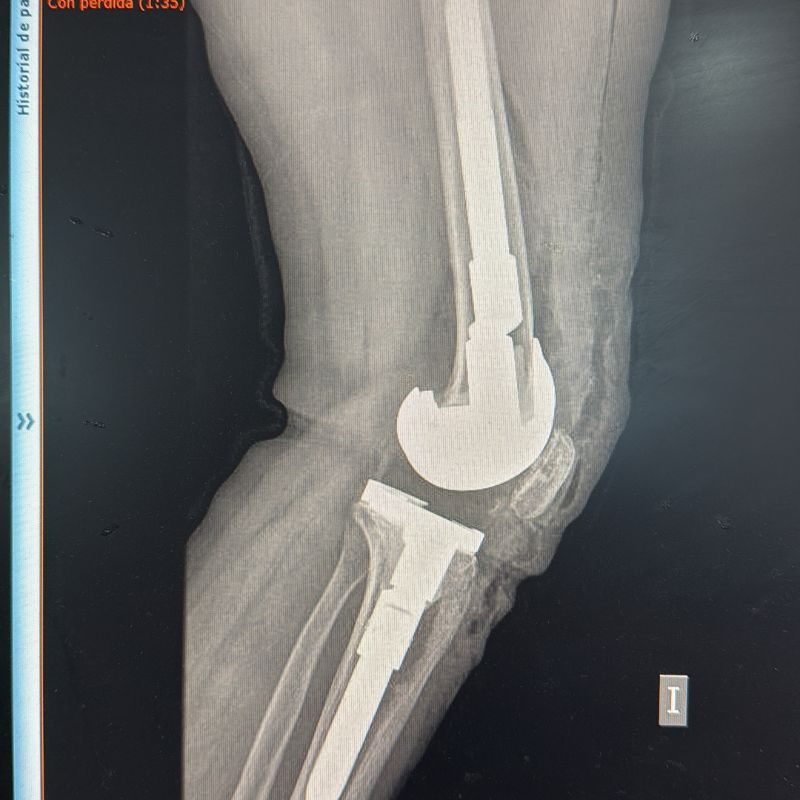

- Prótesis Total de Rodilla.

- Retiro de Prótesis de Rodilla dolorosa o fallida.

- Prótesis de Revisión de Rodilla.